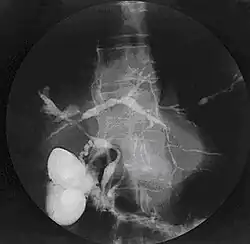

Die eindeutigste Methode ist die Darstellung der Gallenwege mittels ERC (endoskopisch retrograde Cholangiographie). Wegen der relativ hohen Komplikationsrate ist aber heute die bildgebende Methode der Wahl die MRCP (Magnetresonanz-Cholangiopankreatikographie). Auch Autoantikörper, die sogenannten pANCA (perinukleäre antineutrophile zytoplasmatische Antikörper) können typischerweise nachgewiesen werden, sie treten aber nur bei 70 % der Patienten auf.